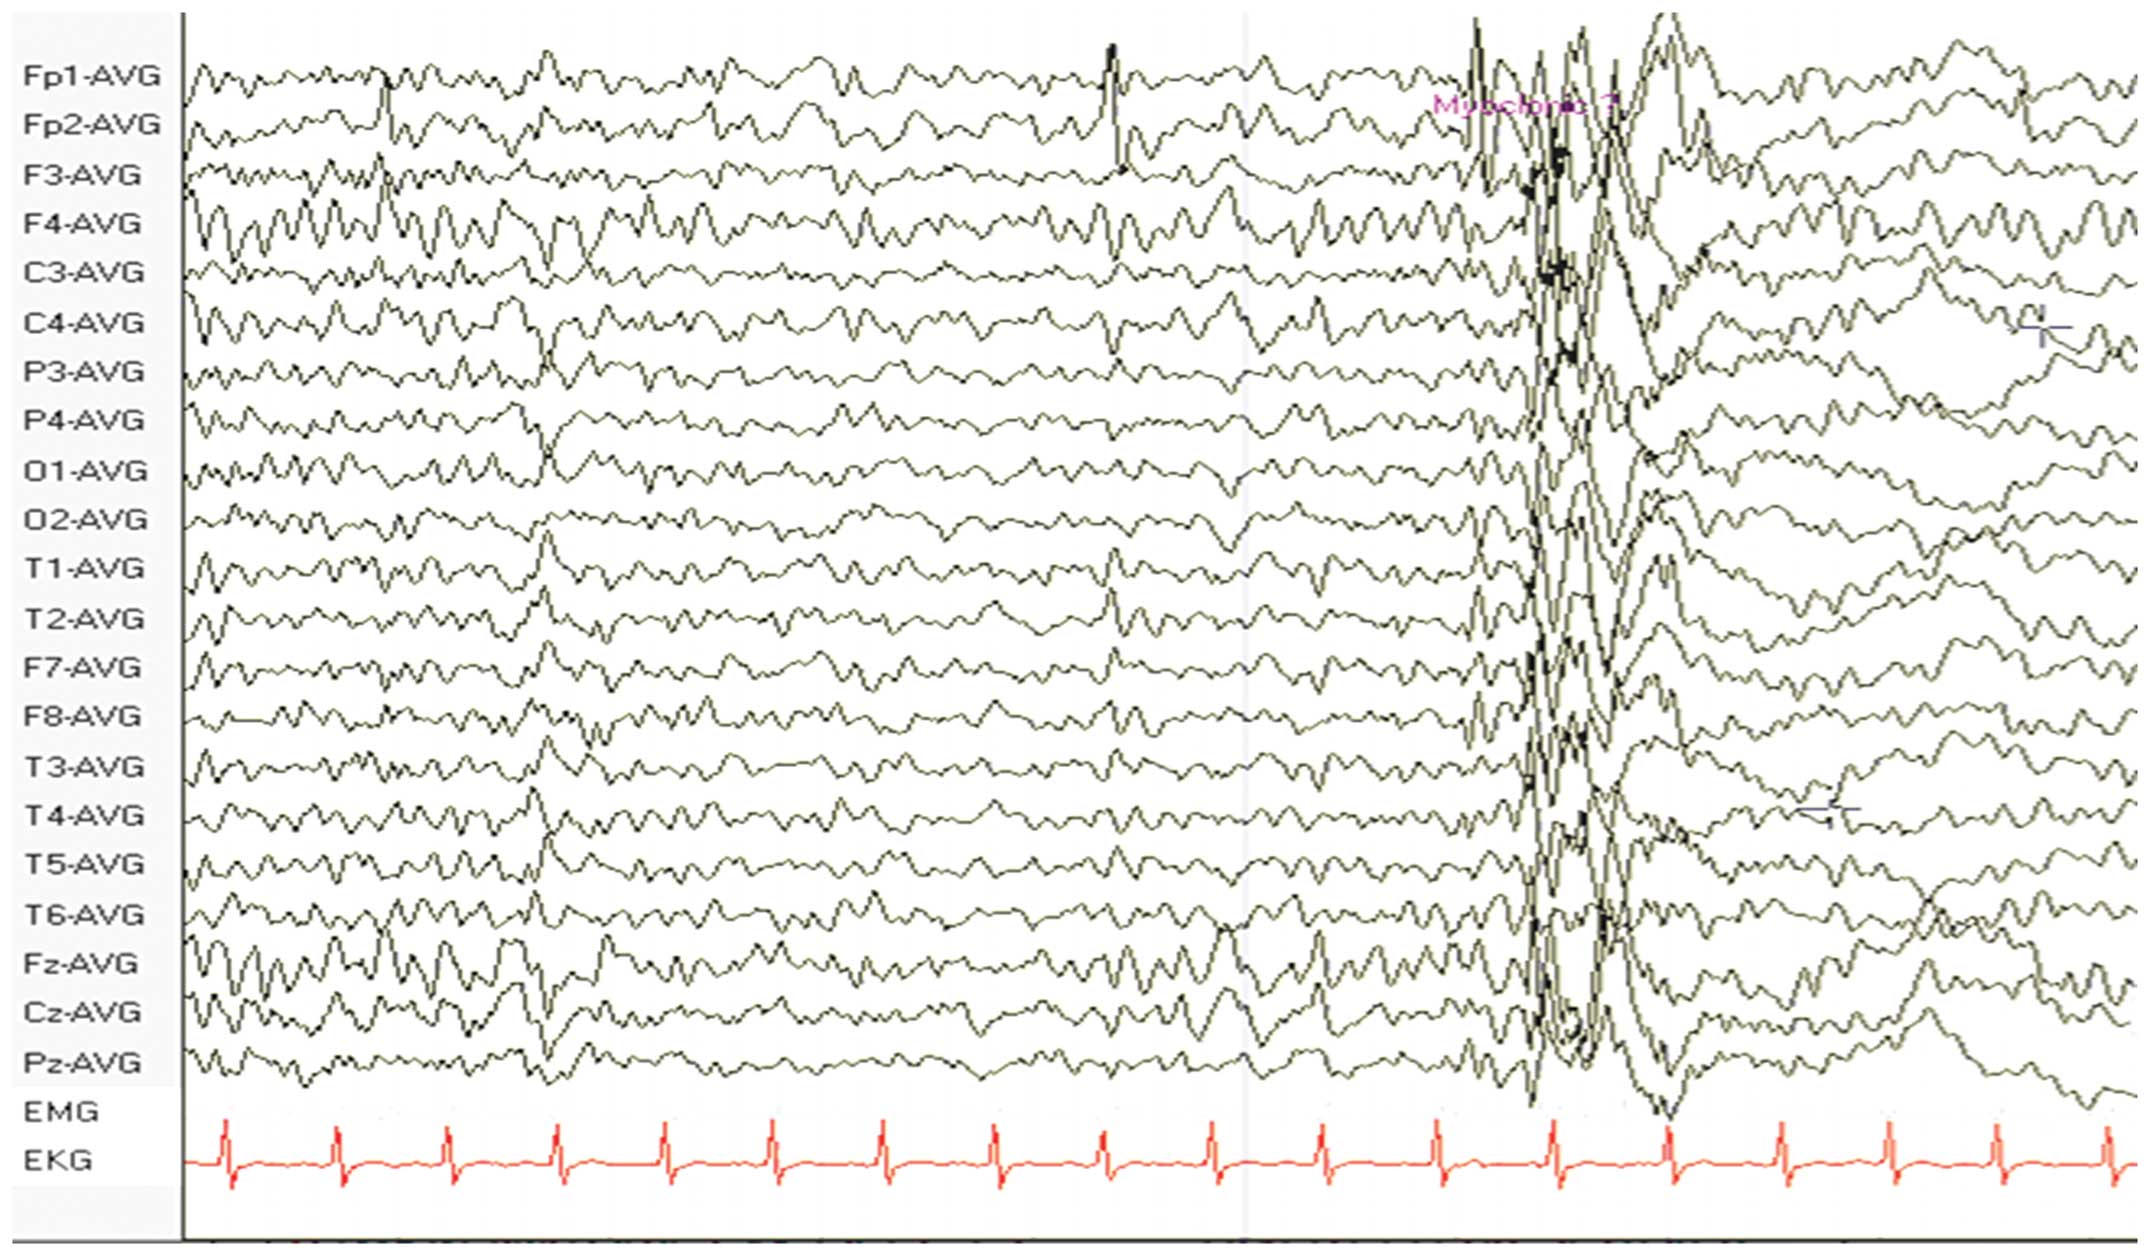

A 25-year-old male presented with paroxysmal left upper limb tics and weakness that had been ongoing for two years. The involuntary limb tics exhibited a sudden onset and lasted for seconds, but were not accompanied by consciousness disturbance. The patient had approximately 10 attacks per day, which were accompanied by limb weakness. A magnetic resonance imaging (MRI) scan was performed initially and was found to be normal. The patient had received irregular diazepam administration from the onset of the disease; however, the symptoms became increasingly more serious. The patient was prescribed 600 mg per day valproate sodium on admission to hospital to control the seizures, but experienced one or two attacks per month subsequent to the administration of valproate sodium. The past medical history of the patient was unremarkable. On examination, the patient was alert and his pupils adjusted to light. Neurological examination revealed intact cranial nerves, but decreased deep tendon reflexes and a decreased sensation of touch, pain and vibration. The gait of the patient was broad and he was unable to walk in a straight line. Full strength was observed in all the muscle groups. The results of the Romberg, heel-knee-shin and finger-to-nose tests were normal. An electroencephalogram (EEG) revealed diffuse spikes and slow waves, predominantly in the frontal and temporal lobes (Fig. 1). A further MRI scan was performed and revealed increased signal density on T2-weighted imaging and decreased signal density on T1-weighted imaging in the right temporal occipital cortical lesions. Local cortical atrophy was also observed in the left temporal-occipital cortex. In addition, the lactic acid concentration (5.2 mmol/l) had markedly increased. The results of the carotid ultrasound and electromyography were normal. A biopsy of the biceps muscle demonstrated a variation in fiber size and the presence of ragged-red fibers (Fig. 2). In addition to the prescribed 600 mg per day valproate sodium, the patient was administered 10 mg per day coenzyme Q10 for approximately 2 years. Two years later his symptoms relieved and an EEG showed less spikes and slow waves than it had previously shown.

The present case report described a young male with involuntary tics and a diagnosis of MERRF based on EEG findings (8). Notably, the patient also presented with a number of associated symptoms, including weakness and a broad gait while walking. In a previous study (9), abnormal brain MRI observations were reported in patients with mitochondrial encephalomyopathy. The most frequent abnormalities in patients with mitochondrial encephalomyopathy are widespread white matter hyperintensity and supratentorial cortical and cerebellar atrophy. In certain cases (10), brain abnormalities are absent. In the present case, the first MRI scan was normal. The patient subsequently developed right temporal-occipital cortical long T1 and T2 signals in the MRI scans. Local cortical atrophy was also observed in the left temporal-occipital cortex. This observation was consistent with brain MRI abnormalities in patients with mitochondrial encephalomyopathy.